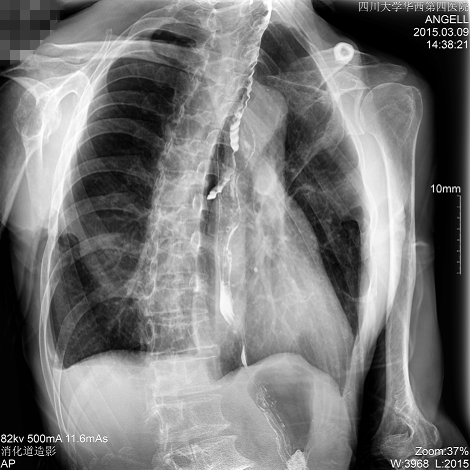

如下圖所示:該患者因吞咽時感到很難受,進(jìn)食時也經(jīng)常咳嗽故就醫(yī)診斷。使用多功能dr為病人進(jìn)行消化道造影診斷,要求他吞鋇后發(fā)現(xiàn),食道各段通過順利,形態(tài)規(guī)則,雙側(cè)梨狀窩不對稱左側(cè)稍淺,多次吞咽動作后,仍見鋇劑滯留,并見鋇劑進(jìn)入氣管,屬于會厭征陽性。會厭功能紊亂,鋇劑進(jìn)入了氣管。

多功能dr正位影像圖

圖為正位:通過動態(tài)影像可以清楚看到鋇劑進(jìn)入了支氣管道且雙側(cè)梨狀窩不對稱